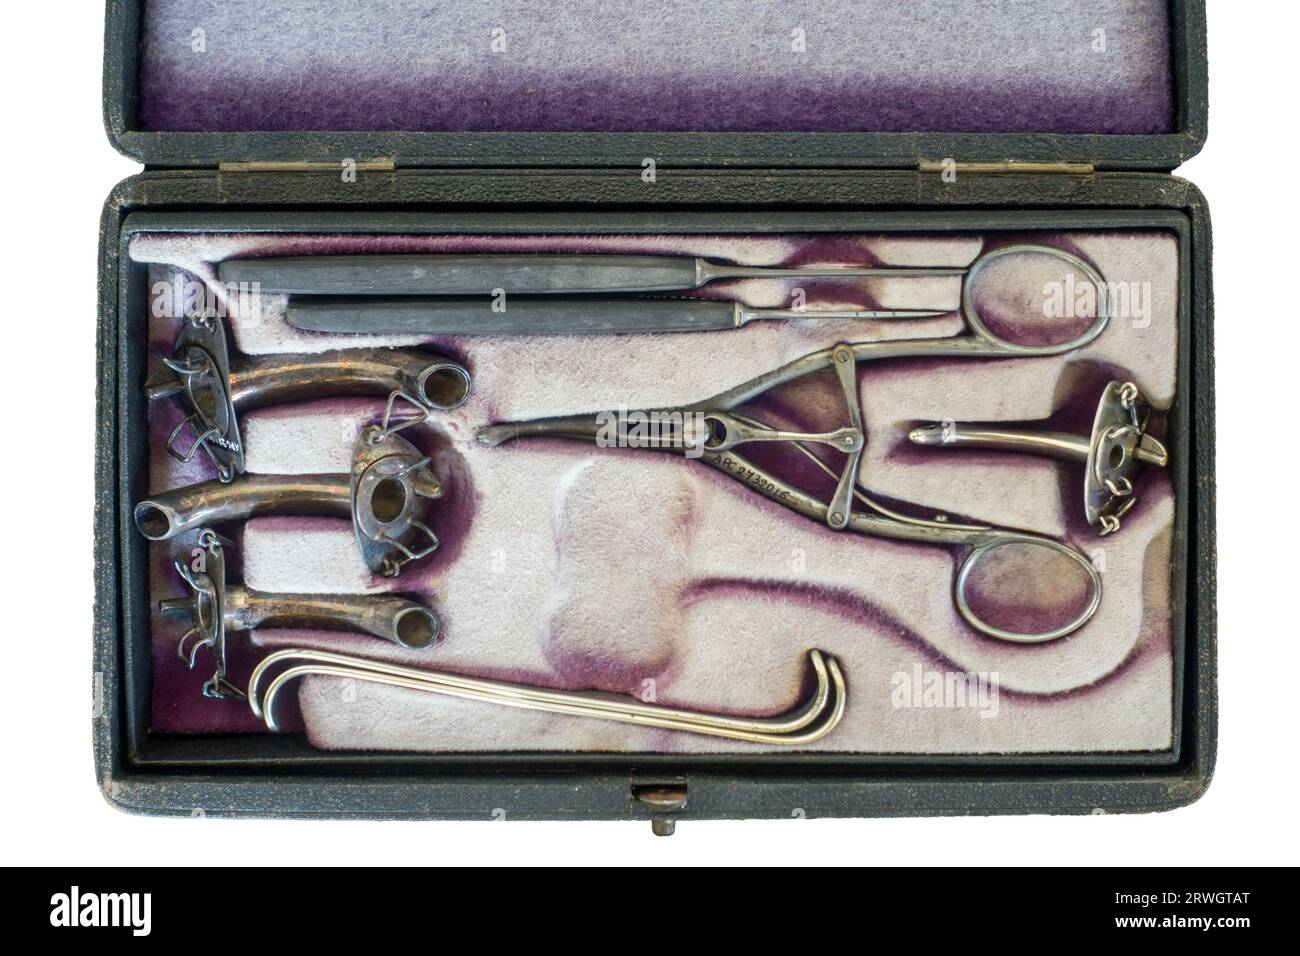

Antique tracheotomy / tracheostomy instruments in box showing tracheal tubes / tracheostomy tubes for treating severe airway obstruction Stock Photohttps://www.alamy.com/image-license-details/?v=1https://www.alamy.com/antique-tracheotomy-tracheostomy-instruments-in-box-showing-tracheal-tubes-tracheostomy-tubes-for-treating-severe-airway-obstruction-image566468528.html

Antique tracheotomy / tracheostomy instruments in box showing tracheal tubes / tracheostomy tubes for treating severe airway obstruction Stock Photohttps://www.alamy.com/image-license-details/?v=1https://www.alamy.com/antique-tracheotomy-tracheostomy-instruments-in-box-showing-tracheal-tubes-tracheostomy-tubes-for-treating-severe-airway-obstruction-image566468528.htmlRM2RWGTAT–Antique tracheotomy / tracheostomy instruments in box showing tracheal tubes / tracheostomy tubes for treating severe airway obstruction